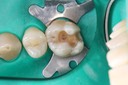

Russ Tabata #30 pre-op

Russ Tabata #30 amalgam removal

Russ Tabata #30 prep